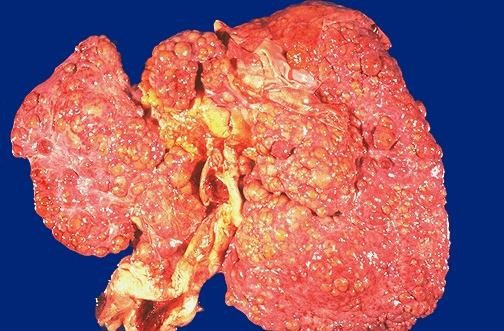

Macronodular & Mixed Cirrhosis

• Nodules are greater than 3 mm in diameter and vary considerably in size

• Usually contain portal tracts and efferent veins

• Liver is usually normal or reduced in size

• Mixed pattern if both types of nodules are present in equal proportions

Macronodular cirrhosis